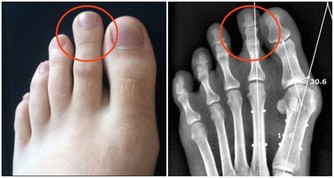

足底筋膜炎的症狀 不少民眾清晨起身時腳一著地,腳後跟劇痛不堪,一段時間後自然好轉,但工作或運動後疼痛感又反覆出現。

這種疼痛大多發作於腳後底內側,雖不致於影響行走,但對於患者的日常生活而言仍是非常困擾。

緩解足底筋膜炎的四種練習 這種「腳後跟劇痛」絕大多數與「足底筋膜炎」有關,腳跟承受全身重量,長年伸展擠壓之後,易造成發炎現象,由於疼痛感如針刺般,也多稱為「足跟痛」或「跟骨骨刺」,患者除適當休息外,應進行適量的伸展運動,根據《FootLogics》報導指出,以下三種簡單練習,澳州骨科醫師及物理治療師建議足底筋膜炎患者在家練習,一般民眾鍛鍊也有預防作用: